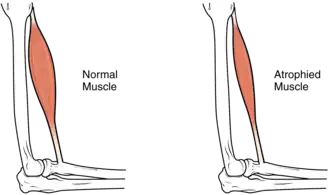

Most infants with CMD will display some progressive muscle weakness or muscle wasting (atrophy), although there can be different degrees and symptoms of severeness of progression. The weakness is indicated as hypotonia, or lack of muscle tone, which can make an infant seem unstable.[1][5] Eventually, most patients develop joint contractures or fixed joint deformities.[6]

Another form of CMD is rigid spine congenital muscular dystrophy (RSMD1), or rigid spine syndrome, which is caused by mutations in the SELENON gene encoding for selenoprotein N.[13] The exact function of selenoprotein N is unknown, but it is expressed in the rough endoplasmic reticulum of skeletal muscle, heart, brain, lung, and placenta tissues, as well as at high levels in the diaphragm.[13] RSMD1 is characterized by axial and respiratory weakness, spinal rigidity and scoliosis, and muscular atrophy, and while it is a rare form of CMD, SEPN1 mutations are observed in other congenital myopathies.[9]

- CMD with spinal rigidity present at birth can have poor muscle tone and weakness, reduced respiratory capacity, muscles could be deformed, beginning early ages stabilization or slow decline spinal rigidity, limited mobility to flex the neck and spine, spinal curvature and progressing deformity and rigidity joints, minor cardiac abnormalities, normal intelligence.[26]